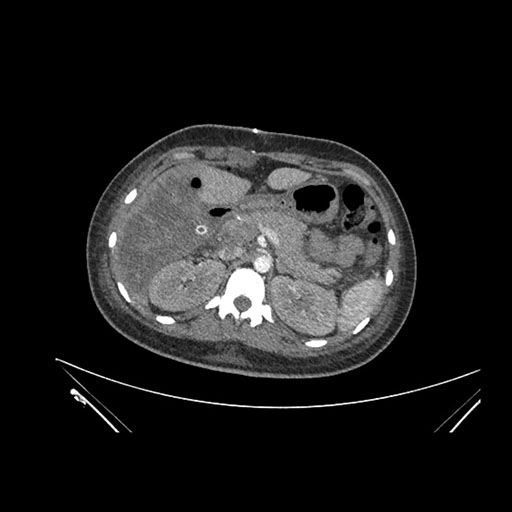

Axial Venous